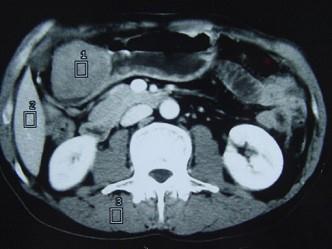

问题 女性,42岁,腹痛、黑便1周,CT扫描见胃窦部圆形块影,最佳的诊断是()

选项 A.胃窦平滑肌瘤 B.胃癌 C.胃淋巴瘤 D.胃窦神经纤维瘤 E.胃内异物

答案 D